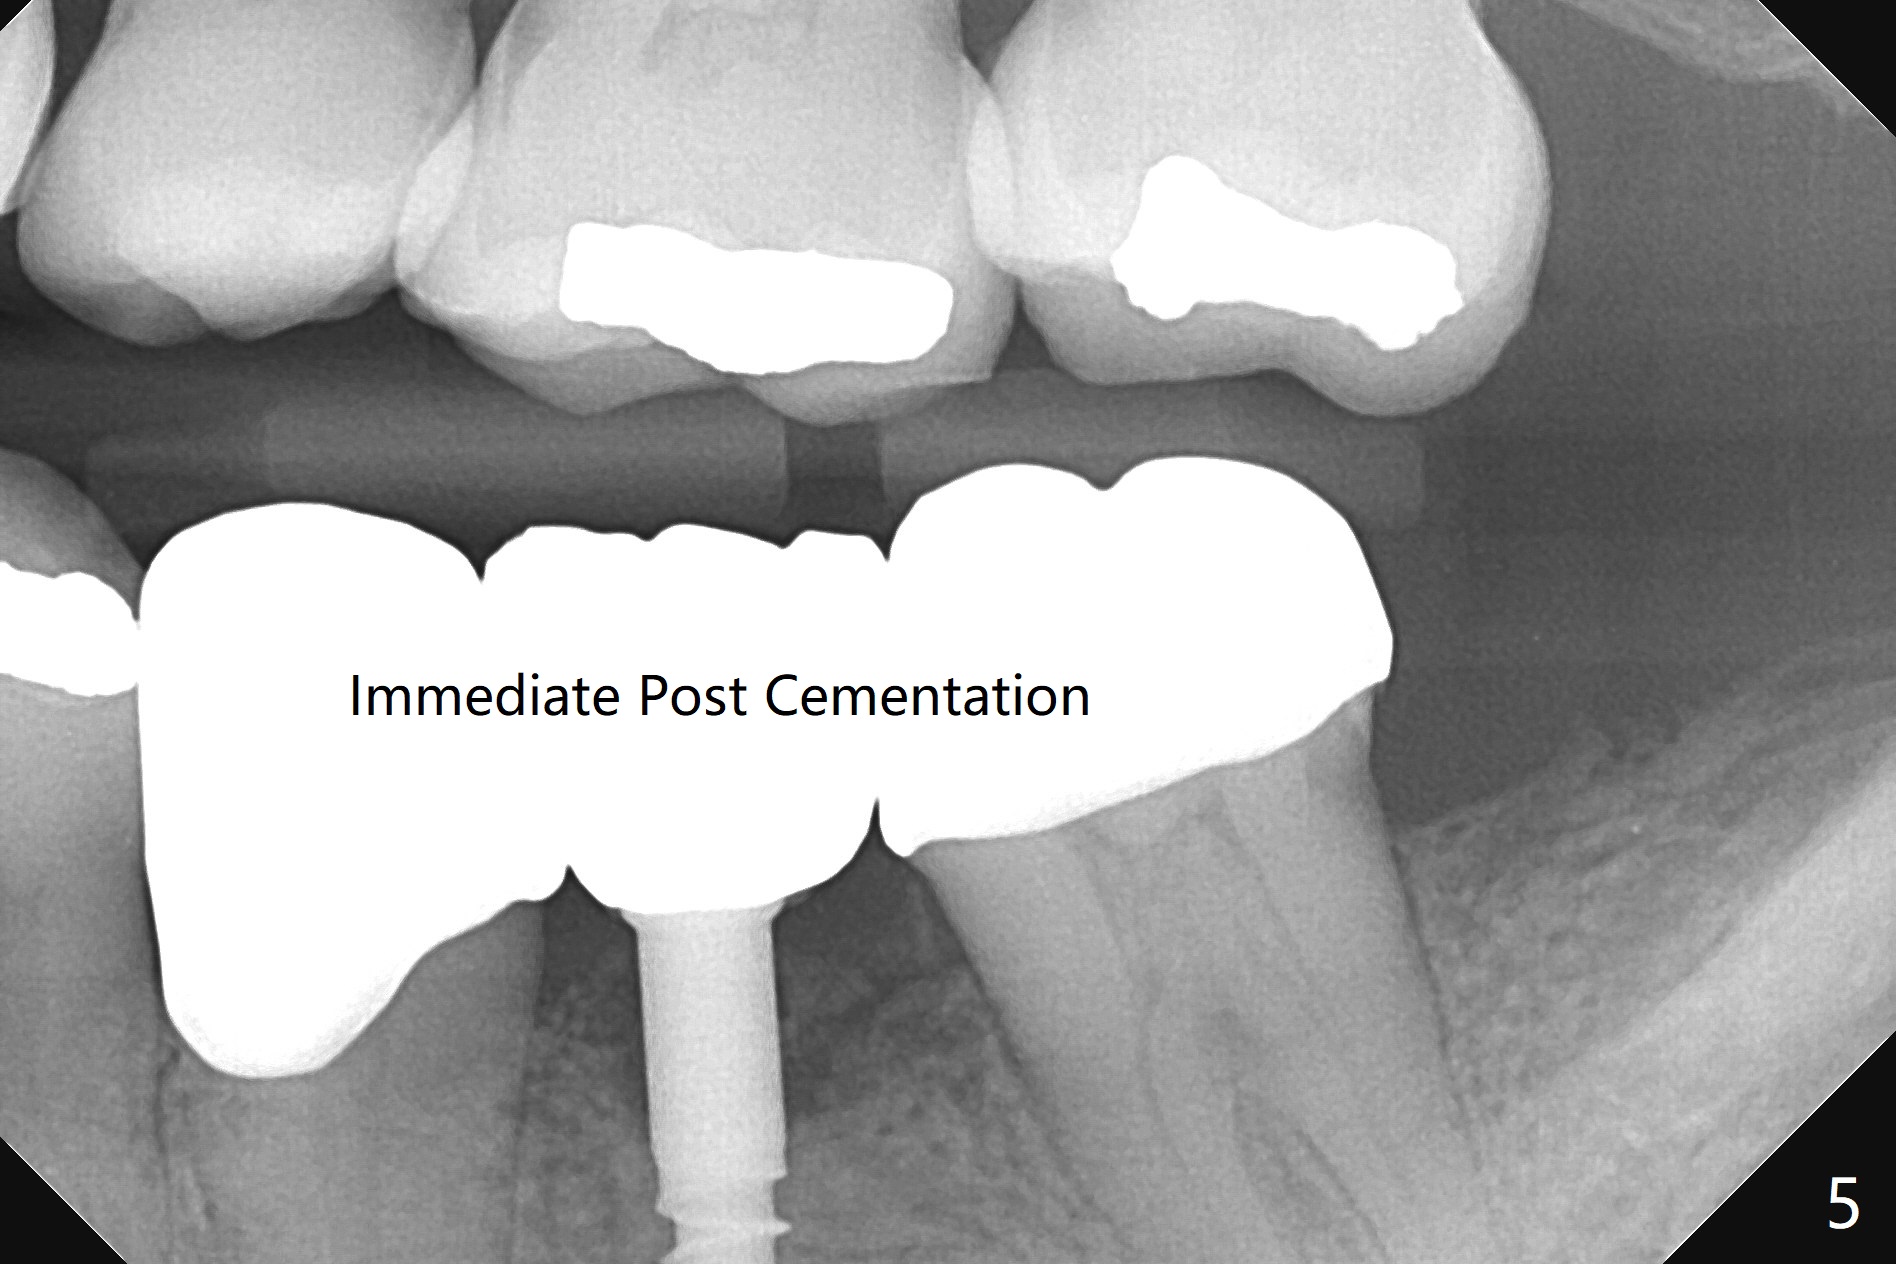

To start osteotomy in the narrow ridge with the oblique top, the latter needs to be trimmed at #19. It would be less traumatic to have a narrow bone trimmer (e.g., 3 mm) in the Narrow Guide Kit. This case is originally designed to have ridge split. The ridge top is trimmed with surgical handpiece after incision. Following pointed drill, the cylindrical part of the 2.2x8.5 mm drill cannot engage to the metal sleeve with 10.5 mm offset. The guide has to be removed. The first 1-2 mm osteotomy has to be done free hand before reuse of the guide and the drill. Nevertheless, the osteotomy is precise buccolingual when it is finished (Fig.1). If the short drill (2.2x7.3 mm) cannot be produced, the next case should have 12 mm offset for narrow guide and an additional guide with regular metal sleeve for tissue punch and bone trimmer. Since the mesiodistal space is also limited, a 2.5x12(4) mm 1-piece implant is placed instead (Fig.2). With the implant placed a little deeper (Fig.3 arrow), bone graft is placed (*), followed by suture. When the procedure is done, the patient is tired. It would be nice to have a more complete Narrow Guide Kit with its own bone trimmer and 2.2x7.3 mm drill. There is no bone loss with retention of bone graft 4 months postop; after reprep of the neighboring teeth, impression is taken (Fig.4). The three crowns are cemented 4.5 months postop (Fig.5).